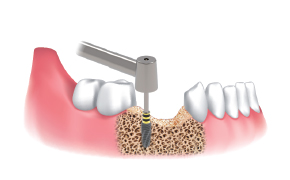

采集顺序 :

使用Ø3.5 / 4.0 / 4.5 / 5.0 / 6.0 Harvesting Drill采集颊骨。

根据直径和临床适应症。

一边注水,一边以300~500rpm的速度钻孔并采集骨片。

在种植体植入部位周围移植采集好的骨片。